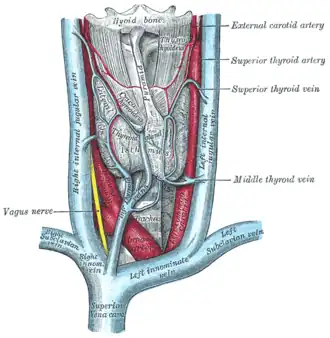

Suprimento de sangue, linfa e nervo

A tireoide é suprida com sangue arterial da artéria tireoide superior, um ramo da artéria carótida externa, e da artéria tireoide inferior, um ramo do tronco tireocervical e, às vezes, por uma variante anatômica da artéria ima da tireoide,[5] que tem origem variável .[11] A artéria tireoide superior se divide em ramos anterior e posterior que irrigam a tireoide, e a artéria tireoide inferior se divide em ramos superior e inferior. [5]As artérias tireoidianas superior e inferior se unem atrás da parte externa dos lobos tireoidianos.[11] O sangue venoso é drenado pelas veias tireoidianas superior e média, que drenam para a veia jugular interna, e pelas veias tireoidianas inferiores. As veias tireoidianas inferiores se originam em uma rede de veias e drenam para as veias braquiocefálicas direita e esquerda.[5] Tanto as artérias quanto as veias formam um plexo entre as duas camadas da cápsula da glândula tireoide.[11]

A drenagem linfática freqüentemente passa pelos linfonodos pré-laríngeos (localizados logo acima do istmo) e pelos linfonodos pré-traqueais e paratraqueais.[5] A glândula recebe suprimento de nervo simpático do gânglio cervical superior, médio e inferior do tronco simpático.[5] A glândula recebe suprimento nervoso parassimpático do nervo laríngeo superior e do nervo laríngeo recorrente.[5]